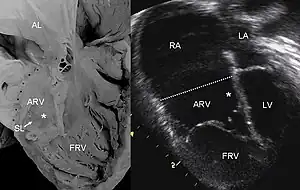

Pathological specimen and ultrasound image of a heart with Ebstein's anomaly: Abbreviations: RA: right atrium; ARV: atrialized right ventricle; FRV: functional right ventricle; AL: anterior leaflet; SL: septal leaflet; LA: left atrium; LV: left ventricle; asterisk: grade II tethering of the tricuspid septal leaflet | |

- Ebstein's anomaly shows dilatation at atrioventricular junction and aneurysmal fibrous sac asterisk (and echocardiogram asterisk)